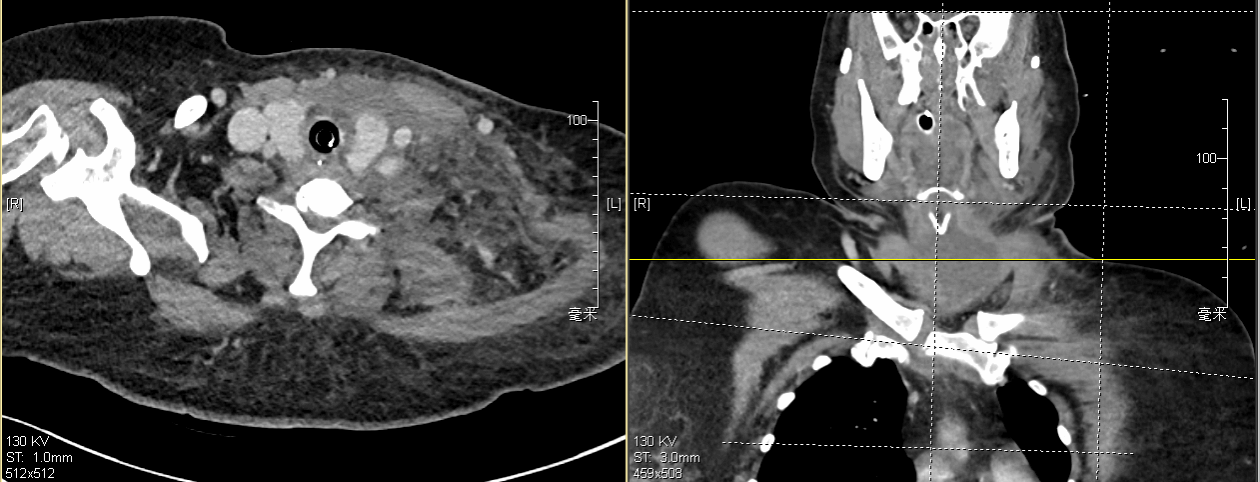

图为患者CT